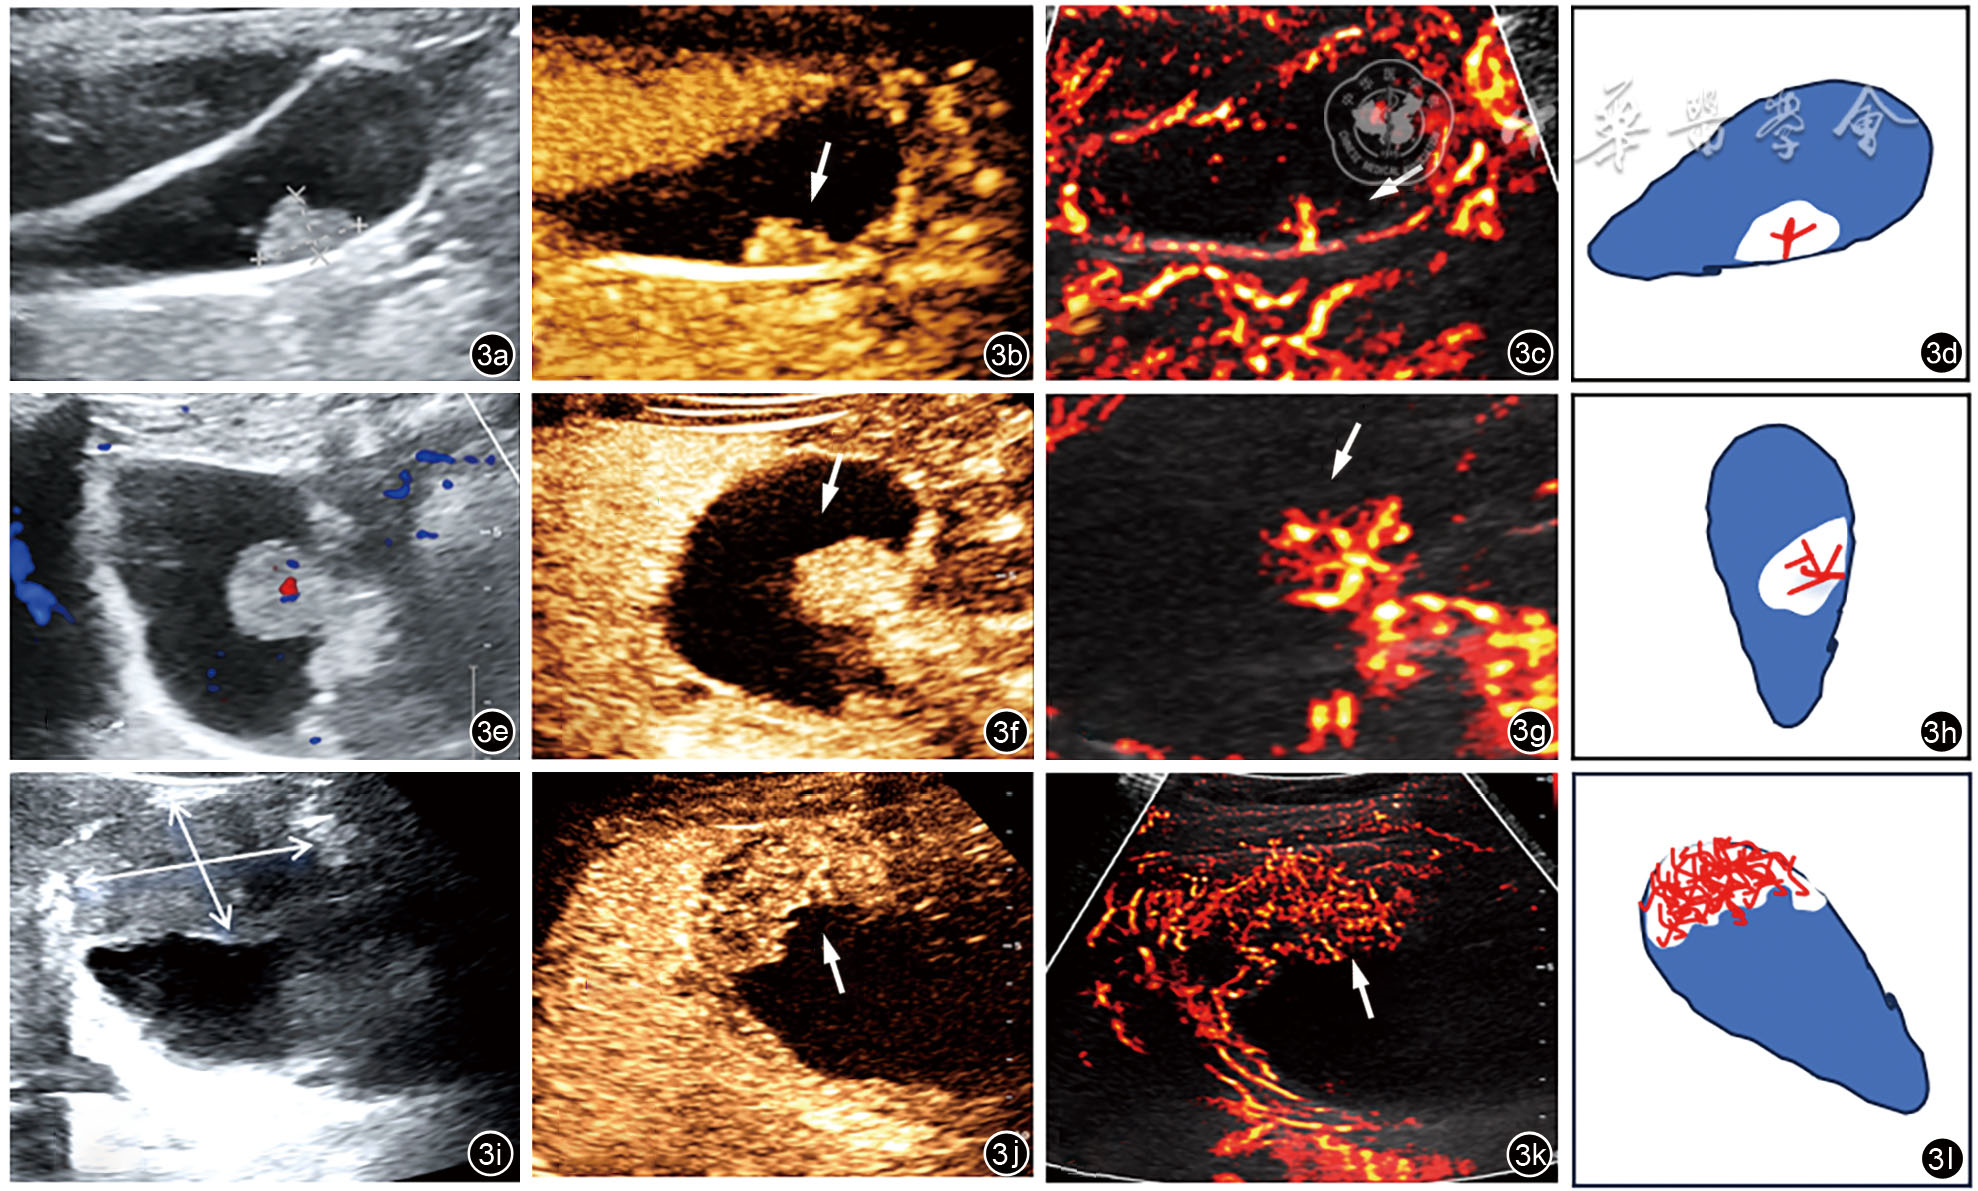

图3 胆囊息肉样病变超声多模态图像及示意图(箭头所示为病变处)。图a为常规超声显示胆囊后壁胆固醇性息肉,最大径>10 mm;图b为超声造影显示该病灶90 s静脉期持续增强;图c为超分辨超声显示病灶内为条棒状血流;图d为示意图显示2级分支,为Ⅰ型血流模式。图e为常规超声显示胆囊后壁胆囊腺瘤,大小18 mm×16 mm,内似见点状血流;图f为超声造影显示该病灶60 s静脉期持续增强;图g为超分辨超声显示病灶内为分支状血流;图h为示意图显示3级分支,为Ⅱ型血流模式。图i为常规超声显示胆囊底部占位,大小45 mm×33 mm;图j为超声造影显示该病灶45 s静脉期早廓清;图k为超分辨超声显示胆囊病灶内丰富杂乱血流;图l为示意图显示病灶内为丰富杂乱血流,为Ⅲ型血流模式